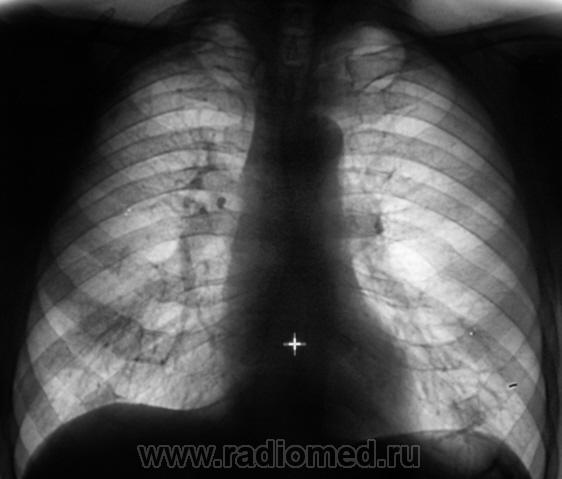

Произведено дообследование.

Пациент направлен на консультацию к фтизиатру. Произведено общеклиническое дообследование, пациент госпитализирован в туб. большицу.